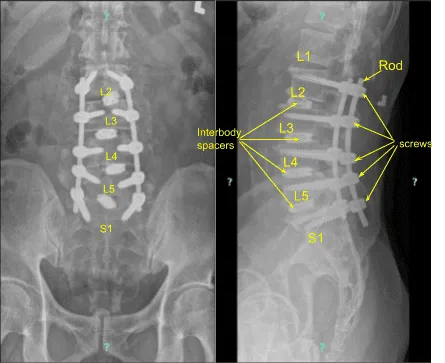

Se realizó una discectomía exhaustiva y se extirpó el disco con una hipófisis. El espacio interdiscal fue irrigado y drenado y rellenado con hueso autoinjerto local y jaulas expansibles rellenas de hueso, insertado espacio discal a la vez y expandido en posición aceptable bajo guía fluoroscópica.

Las varillas se colocaban sobre los tornillos pediculares y se apretaban en su lugar con tornillos de fijación, y finalmente se aprietaban con un destornillador de elevación de torque. Se tomaron las fotos finales y se encontró en una posición aceptable.

La neuromonitorización se mantuvo intacta durante todo el procedimiento. También se realizó un TAC final para comprobar la posición de las jaulas y los tornillos, y se encontró que estaban en una posición aceptable. Tras el cierre, el paciente fue extubado y trasladado a recuperación en estado estable.